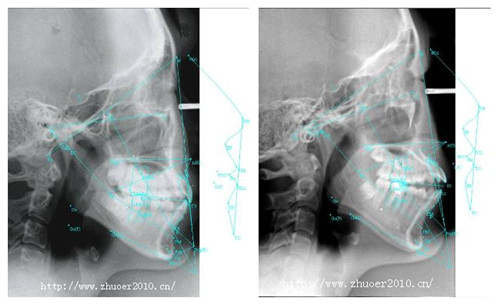

矫治前后X光片比较